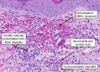

bullous pemphigoid

elderly pts

tense blisters and vesicles

lower abd, thighs, FAs

10-30% involve mucosa

severe pruritis

negativec nikolky sign

rx. topical / systemic CTSDs

Elderly, tense blisters and vesicles

lower abd, thighs, FAs

severe pruritis

negative nikolsky sign

elderly, tense blisters, vesicles

severe pruritis

negative niklosky sign